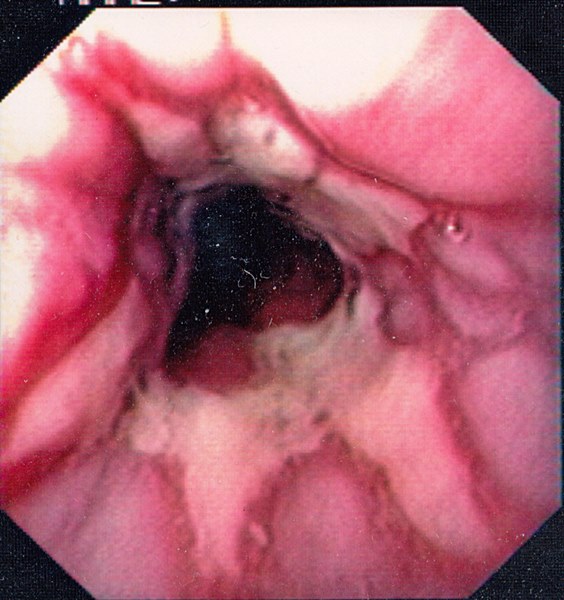

Reflux Oesophagitis Grade D (Los Angeles Classification)